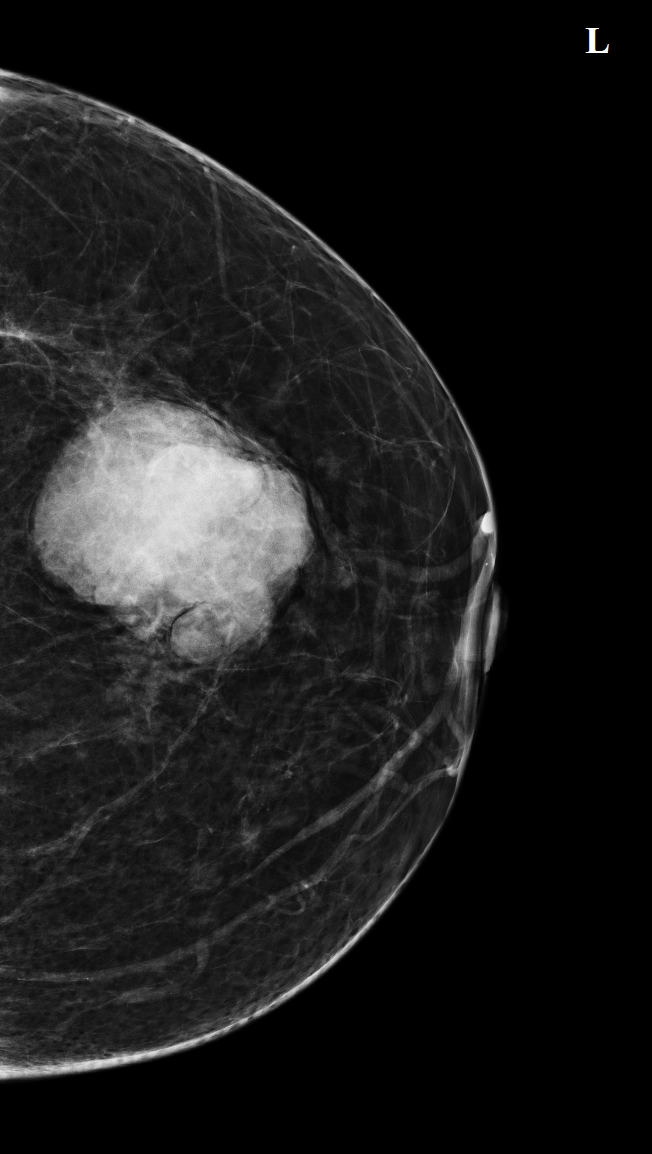

U ác tính

Ung thư biểu mô tuyến vú xâm nhập loại không đặc biệt (Invasive breast carcinoma of no special type)